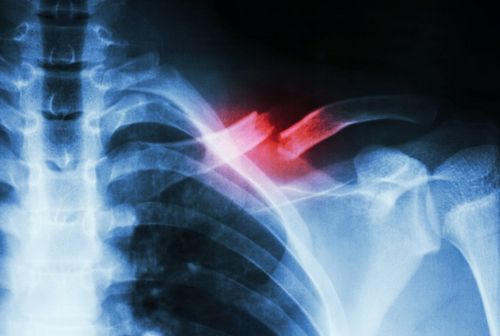

Gãy xương đòn là gãy xương thường gặp nhất ở vùng vai với 35-45% gãy xương vai. Tuy nằm trên một số dây thần kinh và mạch máu quan trọng trong cơ thể nhưng gãy xương đòn ít khi làm tổn thương chúng. Xương đòn cũng rất dễ liền xương nhưng cai lệch nhiều và làm đai vai bị yếu đi do đó các bài tập phục hồi chức năng sau gãy xương đòn là rất cần thiết để khôi phục khả năng vận động của bệnh nhân.

Gãy xương đòn, không phẫu thuật có liền được không?

Em năm nay 33 tuổi. Em bị gãy xương đòn và được bác sĩ tại bệnh viện cho em điều trị bảo tồn. Sau 1 tháng em chụp X quang thì bác sĩ bảo xương đòn của em bị di lệch 1 thân xương và bảo em phải mổ nhưng em có cảm giác mỗi ngày một tiến triển tốt và cử động tay được bình thường.